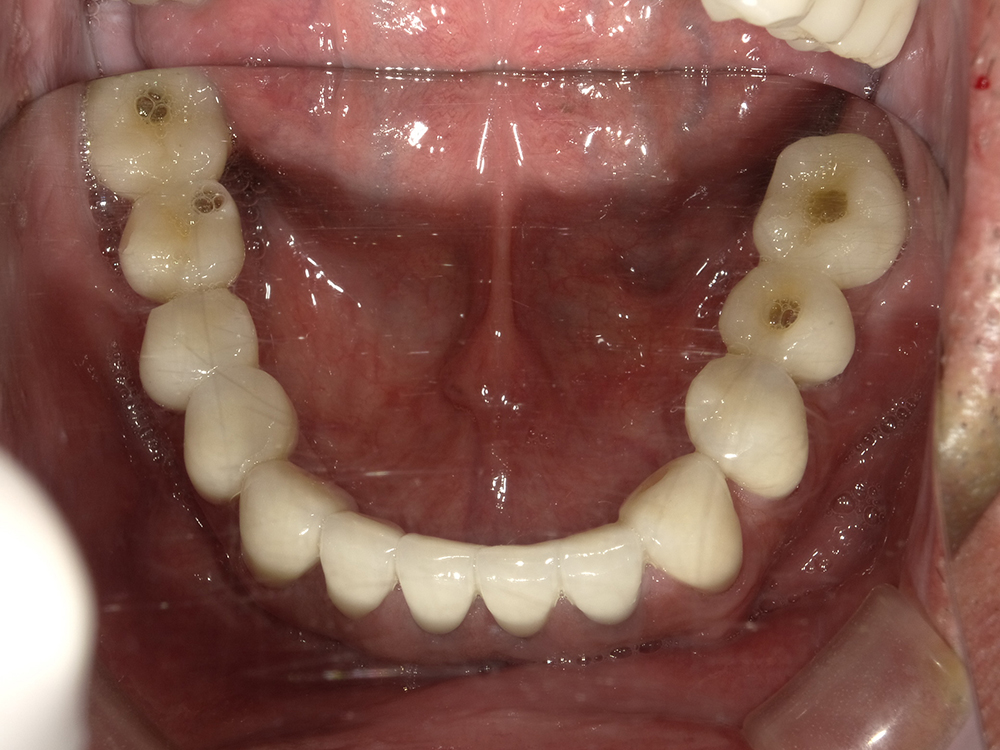

55歳 男性

- 主訴

- 前歯でしか咬めなく、食事を採るのに非常に困難で辛い

- 処置内容

- 上顎6本、下顎3本

- 治療費用

- 上顎:約230万(税込)下顎:約120万(税込)

- 治療期間

- 上顎:1年(仮歯まで8か月)下顎:8か月(仮歯まで5か月)

- リスク

- 上部構造物、仮歯の破折、術後の腫れ(3日)、人工歯根脱落リスクがあります